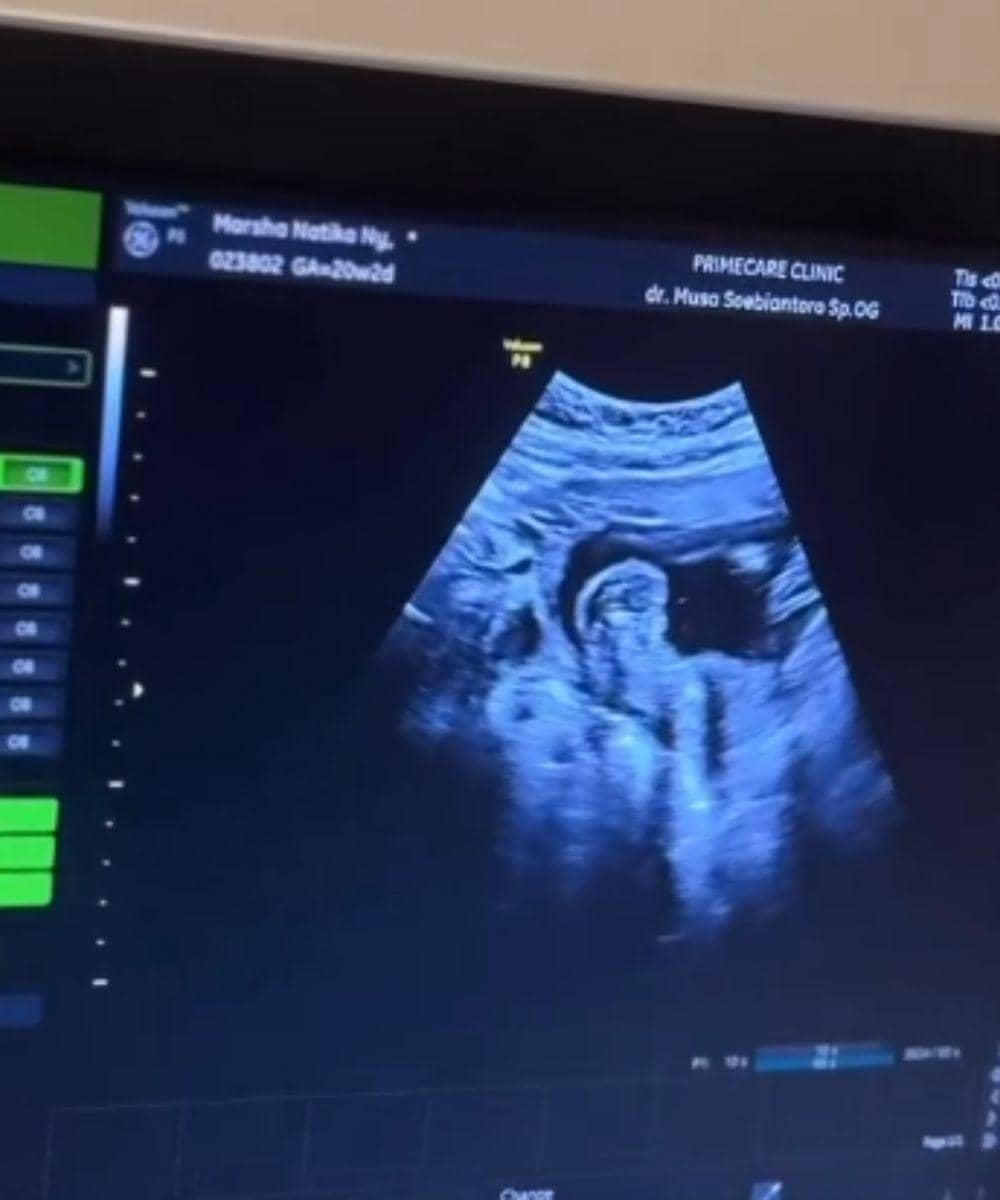

4. Marsha menjalani pemeriksaan USG fetomaternal

Melalui akun Instagram pribadi @marshanatika, Marsha membagikan pengalamannya mencoba USG Fetomaternal. Marsha mengaku terkesan karena hasil pemeriksaannya jauh lebih jelas dibanding USG biasa, ditambah penjelasan dokter yang lebih detail sehingga lebih memahami kondisi dan perkembangan bayinya.

USG Fetomaternal merupakan pemindaian Doppler yang digunakan untuk melihat aliran darah pada plasenta, tali pusat, serta organ bayi, sekaligus memeriksa suplai darah ke rahim. Pemeriksaan ini biasanya disarankan jika ibu berisiko mengalami komplikasi seperti preeklampsia yang dapat memengaruhi fungsi plasenta.